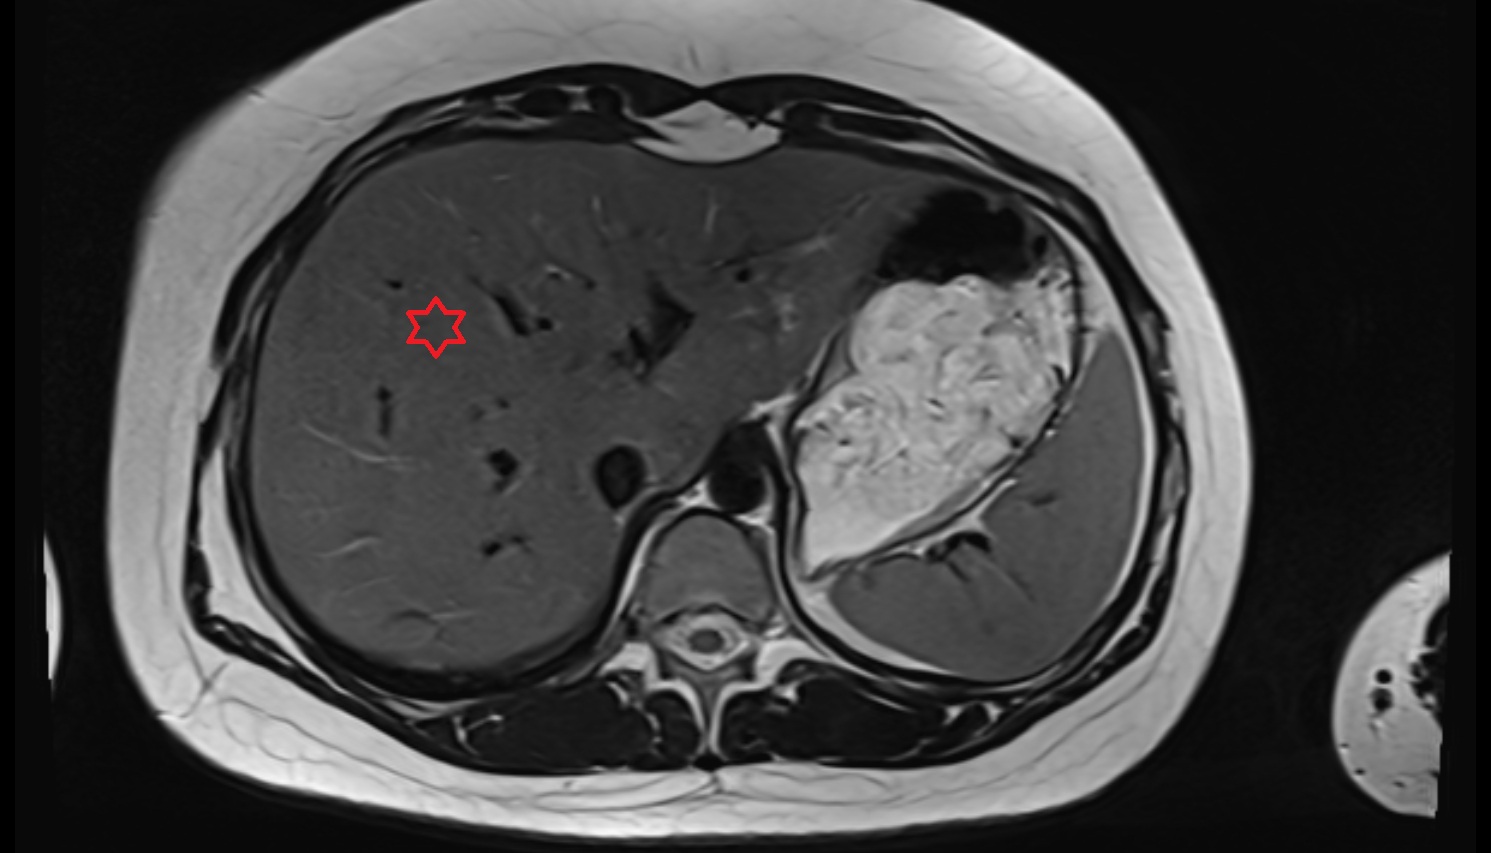

MRI image

Liver Right anterosuperior segment — Segment VIII  MRI  axial  anatomy  image